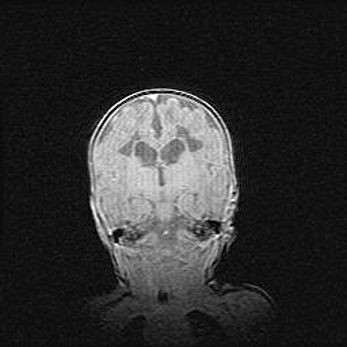

Ниже представлена  галерея МРТ снимков, полученных с применением LMT неонатальных матричных РЧ катушек. Также каждая группа МРТ снимков сопровождается информацией о пациенте (диагноз, возраст, вес, пол, срок гестации) и краткой сопроводительной расшифровкой диагноза.

Наружная гидроцефалия с возможной атрофией височных областей.

Возраст: 28 дней

Вес: 3670 г

Пол: мужской

Окружность головы: 38 см

Срок гестации: 40 недель

Гидроцефалия головного мозга у новорожденных – это заболевание, которое характеризуется скоплением избыточного количества спинномозговой жидкости в желудочковой системе головного мозга в результате затруднения её перемещения от места выработки к месту поглощения в кровеносную систему или вследствие нарушения абсорбции. При открытой наружной форме гидроцефалии у новорожденных расширяются и переполняются субарахноидные пространства.

При нормотензивных  формах,  которые,  как  правило,  являются  следствием  перенесенных ишемических  повреждений  паренхимы  мозга,  возможно  сочетание микроцефалии  с нормотензивной гидроцефалией. В основе данных изменений лежит атрофия больших полушарий с преимущественной  локализацией  в  лобно-височных  областях.